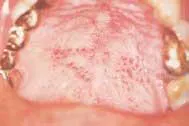

Disease masking is a term that has been applied to describe the appearance of the gingiva associated with chronic smokers.23 Typically, the diseased tissues of smokers tend to have a firmer appearance and less bleeding compared to that of nonsmokers. The term disease masking is used because the vasoconstrictive properties of tobacco smoke hide the inflammatory and destructive changes occurring within the periodontium (See Figures 1a and 1b). The periodontal tissues are compromised by the initial vasoconstriction, resulting in decreased blood flow to the gingiva. This masks the normal early signs of periodontal problems by decreasing gingival inflammation, erythema, and bleeding despite the presence of the disease.